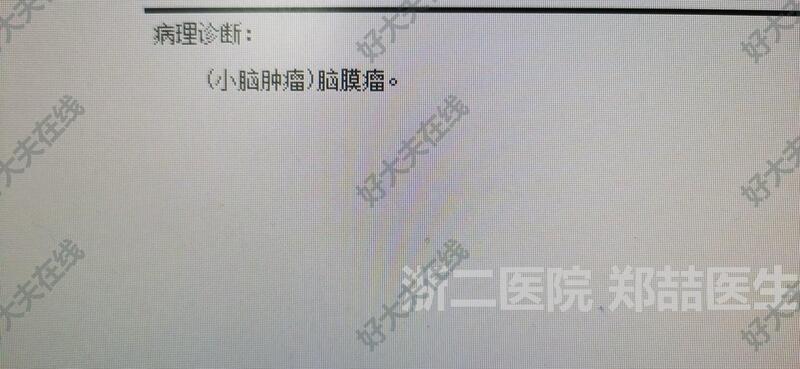

脑膜瘤

71岁男性,头晕1个月,行走不稳,伴恶心呕吐。头磁共振检查发现后颅窝占位。我院报告淋巴瘤或髓母细胞瘤。个人考虑脑膜瘤可能大,基底广泛。

后正中入路,切除肿瘤,基底广泛,冰冻考虑脑膜瘤。